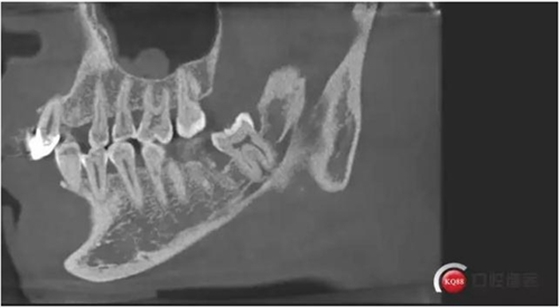

下面?zhèn)惹忻?p style="text-align: center;">